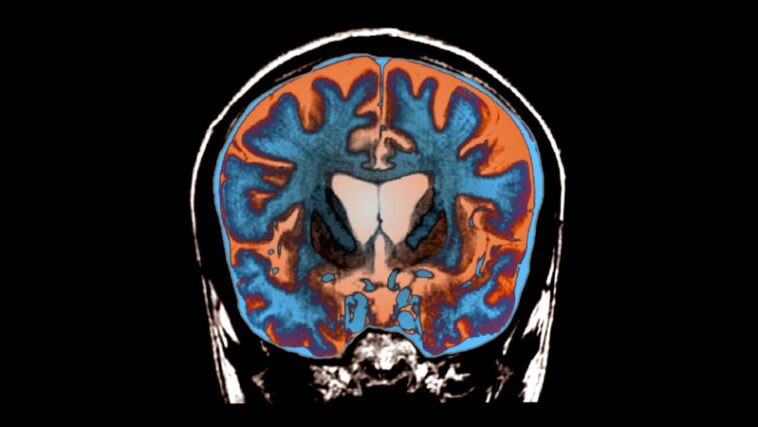

Cette huntingtine élargie est une protéine devenue toxique. Il regroupe dans le cerveau et tue les cellules en grande partie dans les zones cérébrales cruciales pour les mouvements volontaires. Les patients se retrouvent avec des mouvements involontaires croissants, une raideur, des difficultés à parler et à avaler et à un déclin cognitif. Huntington est génétiquement dominant – il ne faut qu'une seule copie du gène défectueux pour le provoquer – de sorte que la progéniture d'un patient a 50% de chances d'hériter de la maladie.

Au cours d'une intervention chirurgicale de 12 à 18 heures, 17 patients présentant des symptômes précoces de la maladie de Huntington ont reçu des injections de charge utile virale en trois endroits de chaque côté des zones cérébrales pertinentes. L'équipe de recherche a ensuite évalué 12 de ces patients pendant 36 mois, testant leurs scores motrices, leur attention, leur mémoire de travail et dans quelle mesure ils pouvaient se passer de leur vie quotidienne. «C'était héroïque, vraiment, au nom des patients et au nom des médecins», explique Snell.